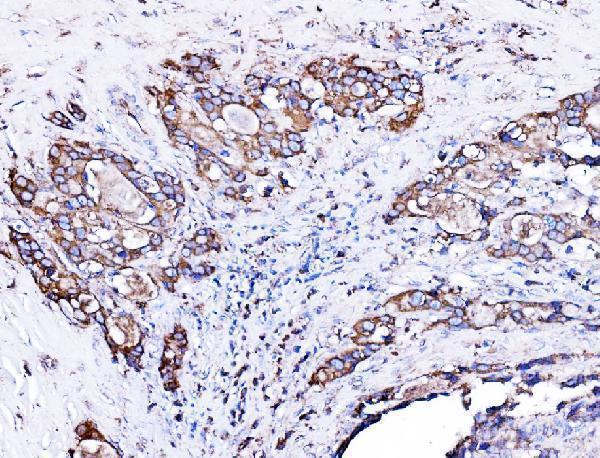

IHC analysis of ORP150/HYOU1 using anti-ORP150/HYOU1 antibody (A04934-2).

ORP150/HYOU1 was detected in a paraffin-embedded section of human gall bladder adenosquamous carcinoma tissue. Heat mediated antigen retrieval was performed in EDTA buffer (pH 8.0, epitope retrieval solution). The tissue section was blocked with 10% goat serum. The tissue section was then incubated with 2 μg/ml rabbit anti-ORP150/HYOU1 Antibody (A04934-2) overnight at 4°C. Biotinylated goat anti-rabbit IgG was used as secondary antibody and incubated for 30 minutes at 37°C. The tissue section was developed using Strepavidin-Biotin-Complex (SABC) (Catalog # SA1022) with DAB as the chromogen.